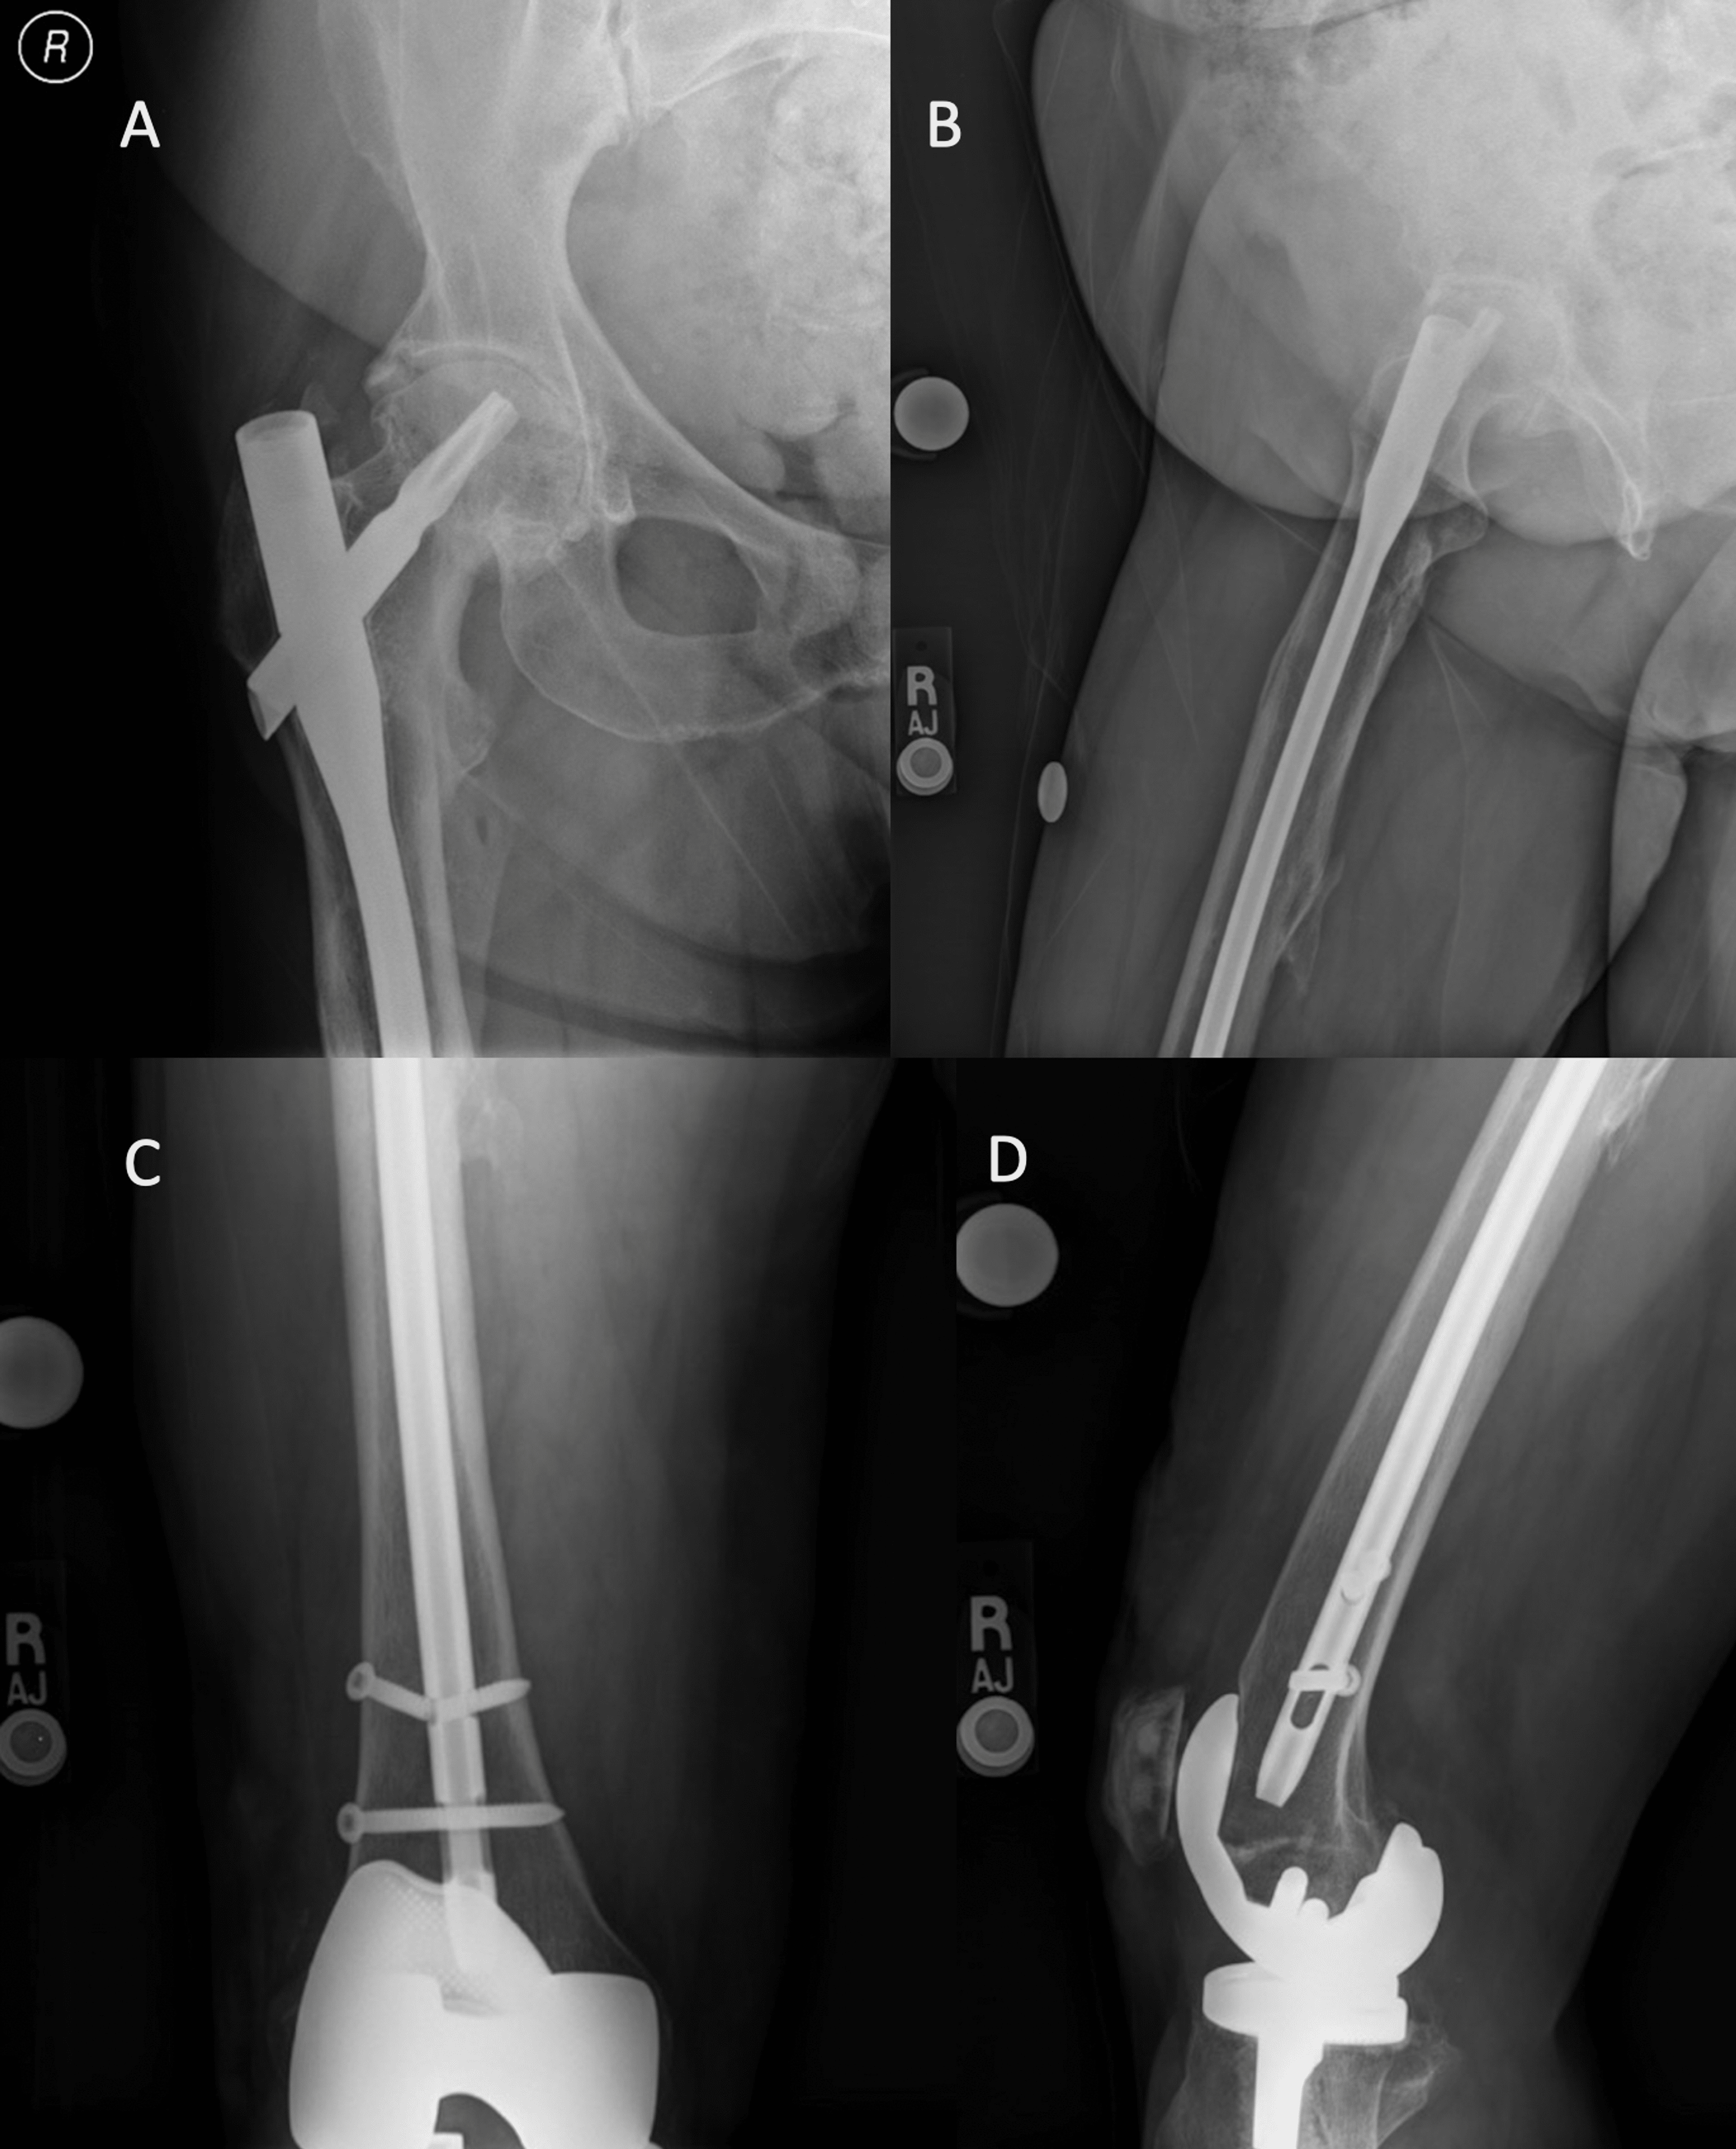

From medapparatus.com

Medical Apparatus Imaging Guide fracture fixation Broken Screw In Shoulder Replacement with the increasing number of total shoulder replacements, periprosthetic (near the implant) fractures are more likely. This surgery replaces the damaged parts. shoulder fractures most often involve the clavicle (collarbone), proximal humerus (top of the upper arm bone), or the scapula (shoulder blade). if the fracture severely damaged your shoulder joint, you may need shoulder replacement surgery.. Broken Screw In Shoulder Replacement.